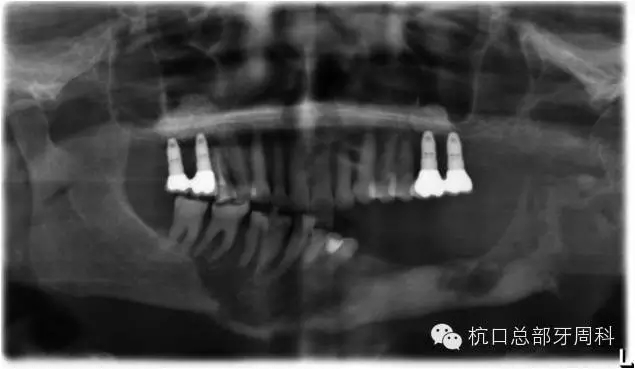

2013.1

114.webp.jpg

2013.3

下頜所有牙齒自動(dòng)脫落,炎癥累及整個(gè)下頜骨,包括左側(cè)髁狀突,病理性骨折左側(cè)聽力喪失

115.webp.jpg